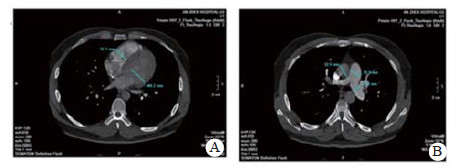

实验室检查结果:动脉血气分析pH 7.458, PaO2 60.5 mmHg, PaCO2 26.7 mmHg, SpO2 92.0%;D-二聚体2 655 ng/mL; BNP 163.00 pg/mL; 血常规WBC 5.91 ×1012/L, NE 73.8%, HGB 138.0 g/L, PLT 286 g/L; 同型半胱氨酸(HCY)14.0 μmol/L (正常值:6~14 μmol/L); 纤维蛋白原定量(FBG) 0.520 g/L(正常值:2.000~4.000 g/L), 纤溶酶原活性39.0%(73.0%~127.0%), 纤溶酶原抑制物-1(PAI-1)6.898 ng/mL(正常均数4.207 ng/mL), 组织纤溶酶原激活物(t-PA) 5.135 μg/L(正常均数2.375 μg/L); 血浆抗凝血酶Ⅲ(AT-Ⅲ:A)、血浆蛋白C活性(PC:a)、血浆蛋白S活性(PS:a)以及狼疮抗凝剂(Lupus anticoagulant, LA)水平在正常范围内。行经胸壁超声心动图检查提示右心扩大(因肺动脉瓣及三尖瓣反流极少, 无法准确估测肺动脉压力), 肺动脉增强CT(pulmonary artery computed tomography angiography, CTPA)提示右室扩大、两肺动脉主干及分支可见多发充盈缺损(图 2)。下肢静脉多普勒超声提示右侧腘静脉急性深静脉血栓形成及右侧股浅静脉血栓形成, 左侧髂静脉及左下肢深静脉未见明显异常。诊断为急性PE(高危组)、KTS。评估后给予重组组织型纤溶酶原激活物(r-tPA)50 mg 2 h内静脉泵入溶栓治疗, 溶栓过程中(r-tPA使用至35 mg时)患者出现咯血约200 mL, 遂被迫停止溶栓治疗, 监测活化凝血时间(accelerated clotting time, ACT)降至200s时给予普通肝素持续泵入并维持ACT于180~220 s, 肝素抗凝治疗48 h后改为低分子肝素(low molecular weight heparin, LMWH)联合华法林治疗, 期间未再发生咯血症状。入院第4天完善肺通气/灌注显像检查, 并提示:左肺下叶, 右肺中叶内段(亚段)、中叶外段、下叶前基底段、外基底段、后基底段血流灌注可见放射性分布稀疏缺损区, 双肺多发PE(累及8个肺段及1个亚肺段), 肺血流灌注受损范围占双肺容积的51%;入院10 d后复查CTPA, 结果显示两肺动脉主干腔内充盈缺损完全消失(图 3)。住院治疗15 d患者好转出院, 院外口服华法林抗凝治疗, 定期监测国际标准化比值(INR), 且维持于PE治疗范围2~3之间。抗凝治疗1年后进行肺通气/灌注显像复查, 提示右肺下叶前基底段、外基底段血流灌注改善, 左肺下叶, 右肺中叶内侧(亚段)、中叶外段、下叶后基底段血流灌注恢复正常。随访3年以来, 患者院外规律服用华法林抗凝治疗, 定期监测INR, 定期复查超声心动图及肺通气/灌注显像检查, 出院3个月超声心动图检查肺动脉压力正常、三尖瓣反流消失; 出院12个月及33个月复查肺通气/灌注未见新发的血流灌注稀疏缺损区, 出院33个月复查双髂双下肢静脉超声未见明显阻塞, 随访期间未出现出血或其他不良事件, 出院1个月后恢复工作至今, 一般状况良好。

| 图 3 患者溶栓后10 d复查CTPA, 右室扩张明显好转(A)、肺动脉增宽有所缓解(B) |